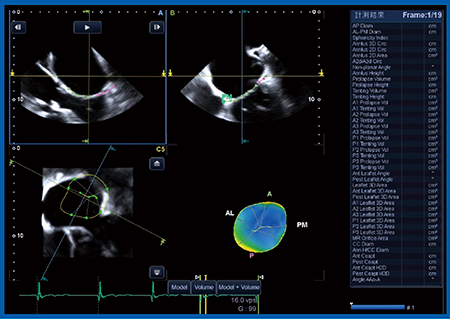

SHDの評価には,3D TEEが最適であると言われている。そこで,実際に,Aplio iシリーズに搭載された最新の3D TEEプローブで1例だけ撮像を行った。

図9は実際の画像であるが,僧帽弁が明瞭に描出されている。Bモードもきれいに描出されており,カラー3Dドプラも含めて,SHDの評価に十分な画像が得られている。さらには,僧帽弁解析ソフトウエアも登場しており(図10),東芝メディカルシステムズ社の3D TEE技術は大きく進化していると思われる。

図9 3D TEEによる僧帽弁の描出

図10 僧帽弁解析ソフトウエアの画面